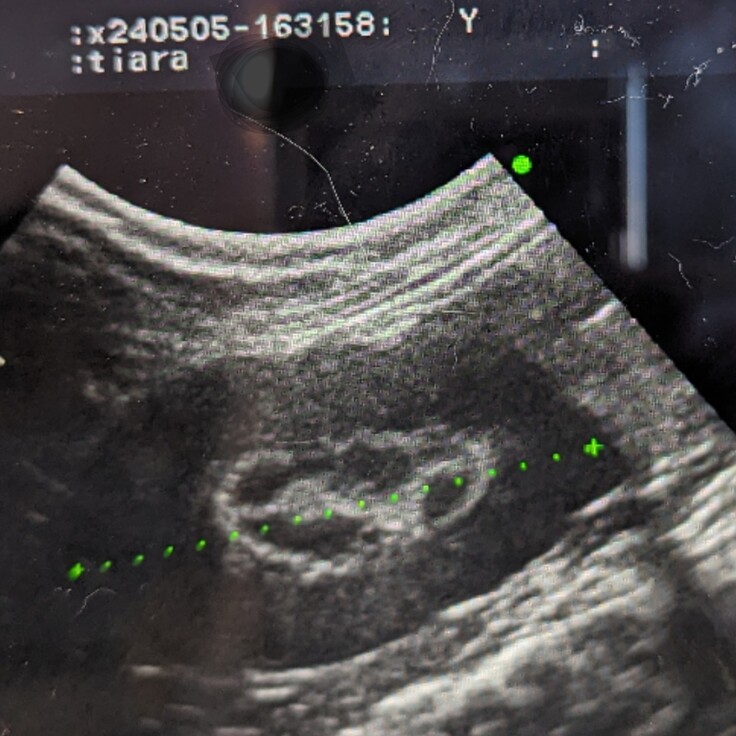

定期検診に行ってきました🏥

昨日になりますが、約半年ぶりの定期検診に行ってきました。

腎臓のリムサインは素人目でも分かるくらいに少し薄くなっていました。ただ検査中にティアラが暴れたので上手く撮れなかったことも否定できないそうです。次の検査でも薄いようなら、もう消えることがないだろうと諦めていたリムサインに少しの光が見えたことになります✨